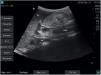

La valoración cualitativa del contenido líquido se puede realizar diferenciando 3 grados. Grado 0: sin contenido líquido en DS ni DLD. Grado 1: contenido líquido solo en DLD, asociándose a contenido gástrico residual. Grado 2: contenido líquido en DS y DLD, asociándose a ingesta líquida.

El riesgo elevado de aspiración pulmonar se asocia a la presencia de contenido sólido y de contenido líquido en un grado 22,3.

Presentamos 3 imágenes ecográficas realizadas con equipo Fujifilm® SonoSite SII y sonda cónvex C60xi de 2-5MHz: antro plano con paredes anterior y posterior unidas (vacío) en DLD, correspondiente con un grado 0 (riesgo bajo) (fig. 1); antro distendido con contenido anecoico (líquido) en DS, correspondiente con un grado 2 (riesgo elevado) (fig. 2) y antro distendido con contenido hiperecoico (sólido) en DS (riesgo elevado) (fig. 3).